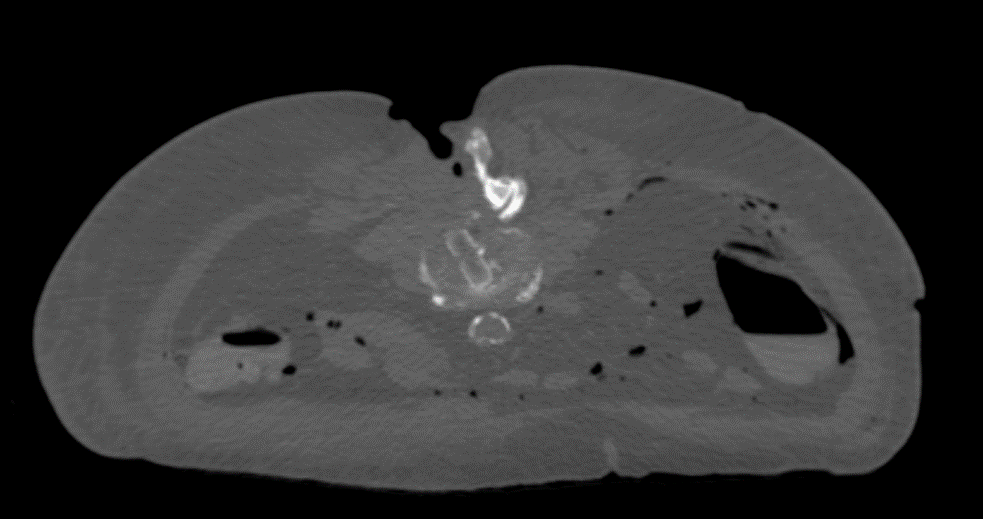

Radiolucency of PEEK

The PEEK core of the PROTI 360° cage has favorable imaging characteristics which support the postoperative assessment of fusion, while the titanium outer layer allows measurement of cage positioning. Clinically, depending on the image quality, plane of view, and patient anatomy, the PROTI 360° cage may show a ghost image of the entire cage on fluoroscopic images (Fig 7). CT images show minimal scatter around the implant (Fig 8).